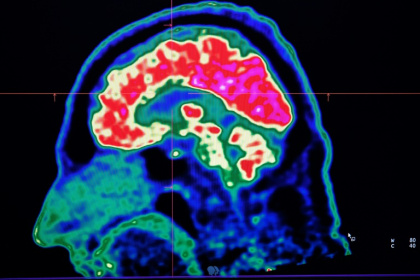

Paris (AFP) - Tiny shards of plastic called microplastics have been detected accumulating in human brains, but there is not yet enough evidence to say whether this is doing us harm, experts have said.

Microplastics are everywhere, but data is still lacking about how they could be affecting our brains - Fred TANNEAU (AFP)